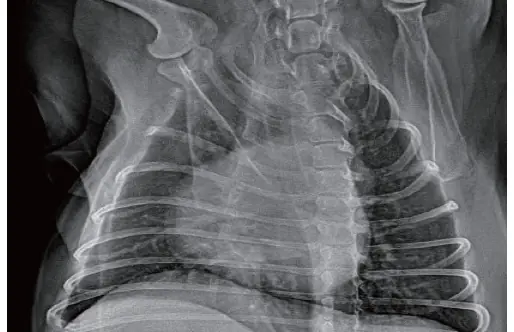

DR

Kenar Keskinleştirme; Çoklu Algoritmalar Araçlar: TPLO/VHS/TTA1